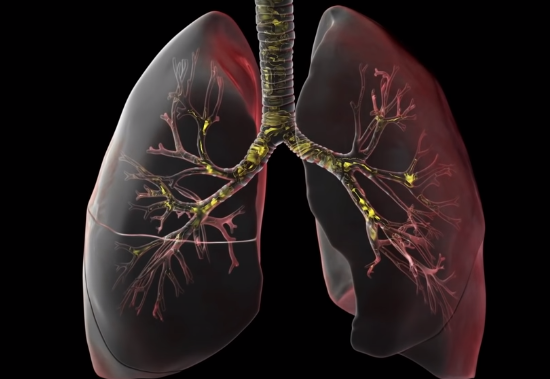

这里为了方便理解,需要看看我们正常的肺部:

肺内部有大量的树枝状气管,逐级变细,直到每个树枝的末端会有一个名叫肺泡的囊状结构。这种富有弹性并且表面布满毛细血管的结构是我们呼吸氧气并排除二氧化碳的基础。

但是,由于战斗的持续,血管通透性增强,血液渗入肺泡,同时在肺泡内会分泌大量黏液。

如果在这个时候,对患者肺部进行CT扫描,我们会看到像下面这样大面积白色区域,医学上称之为“白肺”。这样肺部失去了原有的交换气体功能,最终使正常呼吸变得异常困难。

肺部遍地焦土,这个过程会引起发热、四肢乏力、干咳等症状,其他表现包含鼻塞、打喷嚏、流鼻涕、头痛、咽痛、咳血,咳痰、肌痛,或腹泻等。甚至会引发严重并发症,甚至发生呼吸衰竭,死亡。